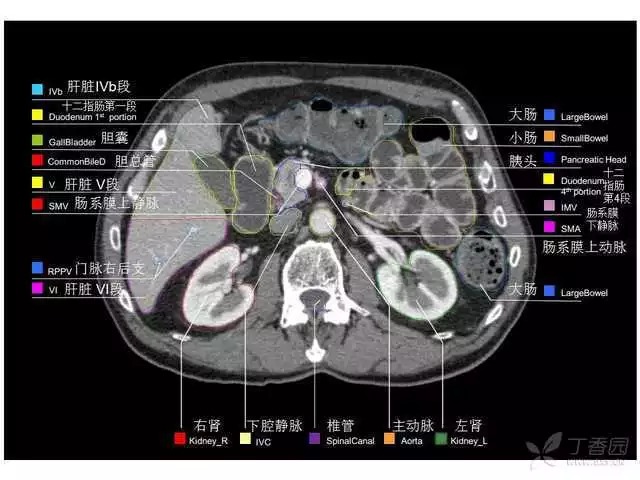

腹部肝脏高清CT断层的图谱

全腹部高清CT图谱,淋巴结彩色图谱,血管解剖图谱大汇总!

肝段,肝内管道的分布规律

美国放射学会ACR官网,对肝脏的区域和节段解剖学概述